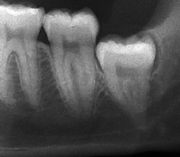

Wisdom teeth likely become impacted because of a mismatch between the size of the teeth and the size of the jaw. Impacted wisdom teeth are classified by their direction of impaction, their depth compared to the biting surface of adjacent teeth and the amount of the tooth's crown that extends through gum tissue or bone. Impacted wisdom teeth can also be classified by the presence or absence of symptoms and disease. Screening for the presence of wisdom teeth often begins in late adolescence when a partially developed tooth may become impacted. Screening commonly includes clinical examination as well as x-rays such as panoramic radiographs.

Impacted wisdom teeth are classified by the direction and depth of impaction, the amount of available space for tooth eruption. and the amount soft tissue or bone (or both) that covers them. The classification structure helps clinicians estimate the risks for impaction, infections and complications associated with wisdom teeth removal.[4] Wisdom teeth are also classified by the presence (or absence) of symptoms and disease.[5]

Impacted wisdom teeth are often described by the direction of their impaction (forward tilting, or mesioangular being the most common), the depth of impaction and the age of the patient as well as other factors such as pre-existing infection or the presence of pathology.[3]:143–144 Of these predictors, age correlates best with extraction difficulty and complications during wisdom teeth removal[6] rather than the orientation of the impaction.[7]